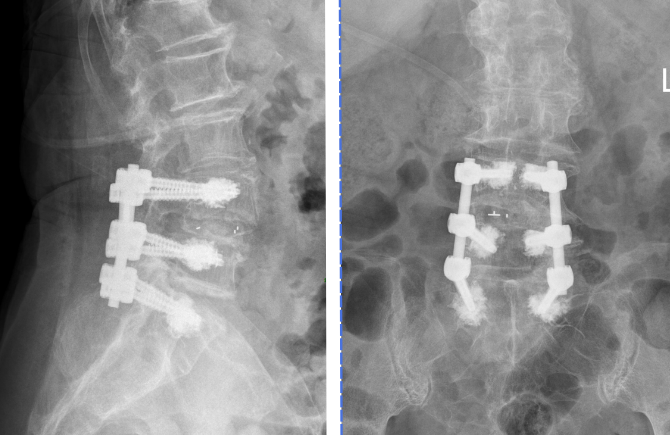

术前影像学资料

“高龄患者,存在明显腰椎滑脱、不稳定,脊柱结构增生、退变,与正常人发生了一些变化,导致血管和神经存在一定程度的移位,且患者骨质疏松严重,术中若使用普通螺钉可能存在钉子松动、拔出等可能,存在复杂的技术难关,对医生的手术操作技巧要求很高!”主管医生卢敏强强调说,

“我们的手术操作能不能解决目前患者症状?手术中及术后可能遇到哪些困难?会不会引起腰椎不稳或者加重不稳?这个不稳处于腰椎失稳的哪个阶段?”主任姜富祥带领大家就几个核心问题展开病例讨论和研究,最终决定实施导航下腰椎后路滑脱复位椎间盘切除+椎板切除减压+脊髓和神经根松解+植骨融合+椎弓根螺钉内固定术+椎板扩大减压术,最终用骨水泥加强螺钉辅助固定。术中借助导航指引下精准定位,使置钉操作过程又快又准,最终手术的每一个环节都进行得十分顺利。